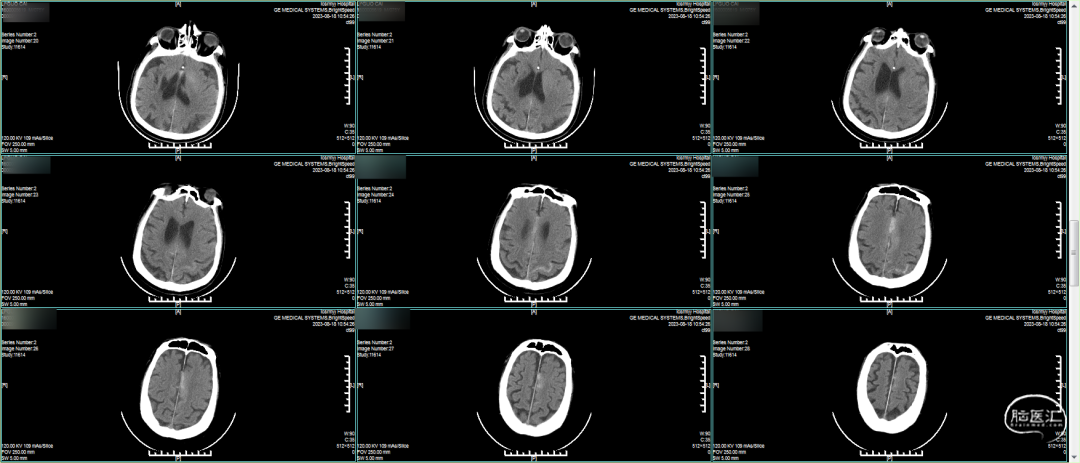

入院急诊头颅CT平扫:右侧基底节区侧脑室旁条索状低密度影,考虑卒中囊,老年性脑改变。

溶栓前CT平扫 :左侧未见确切异常,右侧基底节区为陈旧性脑梗死 。

溶栓后CT平扫:未见出血。